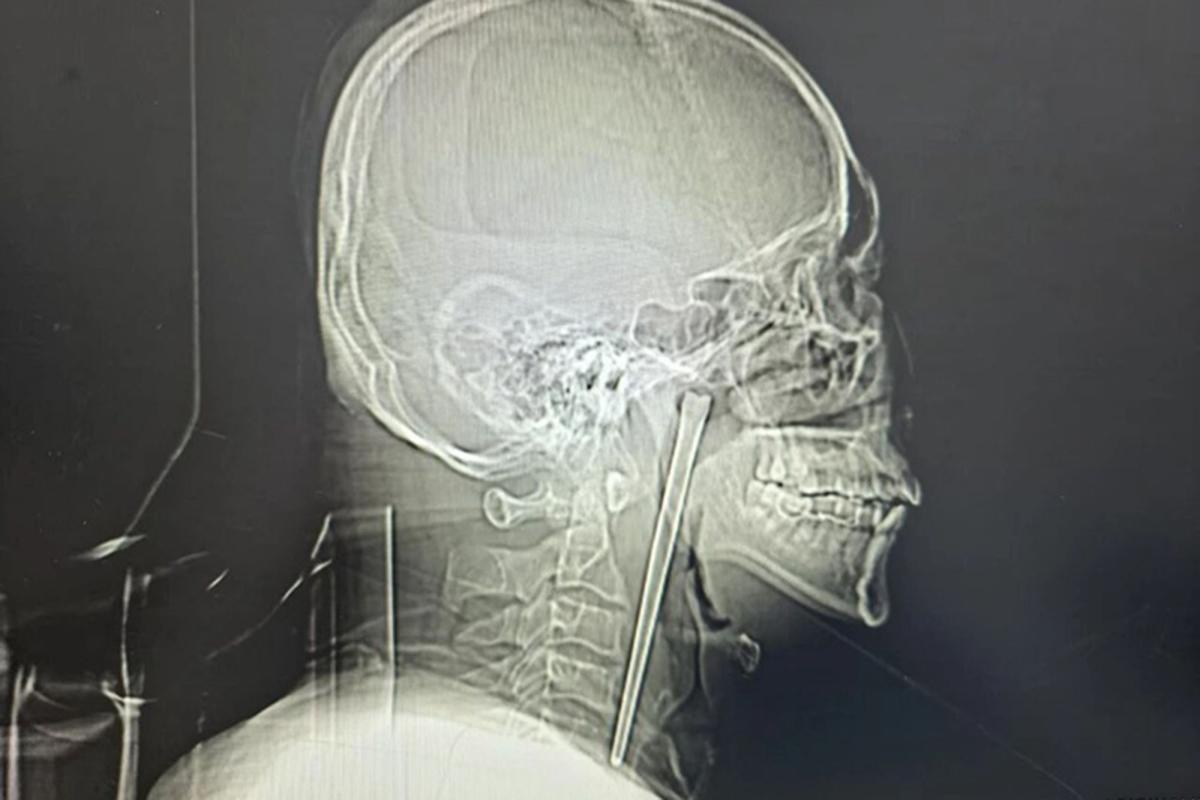

A man in China swallowed a metal chopstick while eating dinner eight years ago and decided to leave it lodged in his throat until a surgeon finally removed it last month, March 2026.

According to a jaw-dropping hospital case study published in March, the “alcoholic” patient, identified only as Mr. Wang, went in for a check-up shortly after gulping down the five-inch utensil in 2018 but refused to have it removed.

Wang, 46, didn’t want doctors to cut his neck open at the time, so he lived with the discomfort for years, the South China Morning Post reported.

Surgeons performed a minimally invasive operation to remove the obstructive object via Wang’s mouth instead of slicing open his neck, according to the hospital’s report.

His vocal cords and nearby mucous membrane were luckily not injured and functioned normally after the surgery, according to the report.

Wang was discharged from the hospital days later and is expected to make a full recovery